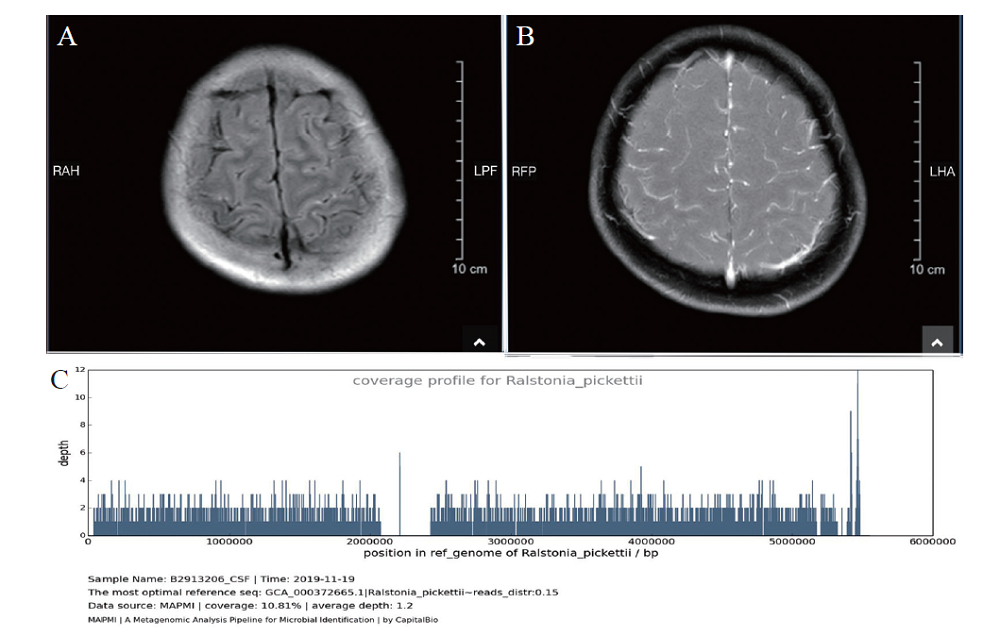

初步考虑临床诊断为病毒性脑膜炎,给予患者阿昔洛韦0.5 g静脉滴注、每8 h 1次。但患者体温升高至39.3℃,头痛加重,并出现神志改变,睡眠时间增多。头颅MRI(2019年11月11日):枕顶叶脑表面异常信号,见图1A;头颅MRI增强扫描(2019年11月15日):浅表脑沟异常强化,见图1B。结合影像学检查,更改诊断为细菌性脑膜炎,于2019年11月12日换用美罗培南2 g静脉滴注、每8 h 1次,患者体温逐渐下降,头痛逐渐缓解。2019年11月15日复查脑脊液压力 265 mm H2O,脑脊液常规及生化:红细胞0,白细胞62×106/L,中性粒细胞22%,淋巴细胞78%,蛋白1.27 g/L,葡萄糖定量2.29 mmol/L,氯125 mmol/L,乳酸脱氢酶40 U/L,腺苷脱氨酶1.60 U/L;脑脊液细菌培养3 d未能发现细菌;血培养及鉴定:需氧、厌氧及真菌培养均阴性。

2019年11月15日采用mNGS检测患者脑脊液标本,在脑脊液中检测到皮氏罗尔斯顿菌(检出序列数 5788,基因组覆盖度 59 940 bp/10.81%,估测浓度1.1×103 copies/ml),见图1C,继续给予美罗培南治疗。2019年11月25日再次复查脑脊液压力150 mm H2O,脑脊液常规及生化:红细胞0,白细胞8×106/L,蛋白0.45 g/L,葡萄糖定量2.55 mmol/L,氯123 mmol/L。经治疗后患者好转,并于2019年11月28 日出院,最终诊断为皮氏罗尔斯顿菌脑膜炎。患者出院后无继续服用药物,随访3个月,无复发。

图1 一例皮氏罗尔斯顿菌脑膜炎患者的头颅MRI及脑脊液mNGS结果

A:头颅MRI示枕顶叶脑表面异常信号;B: 头颅MRI增强扫描示浅表脑沟异常强化;C: mNGS结果